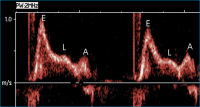

Gepulster Doppler - Mitraldoppler

Abbildung 3: Gepulster Doppler - Mitralklappe: Restriktives Flußprofil mit hoher E-Welle, rascher Dezeleration der E-Welle, E/A-Amplitude > 2 und Zeichen der verzögerten myokardialen Relaxation (L-Welle) im Anschluß an die E-Welle.

Keywords: DopplerEchokardiogrammKardiologieMitralklappe